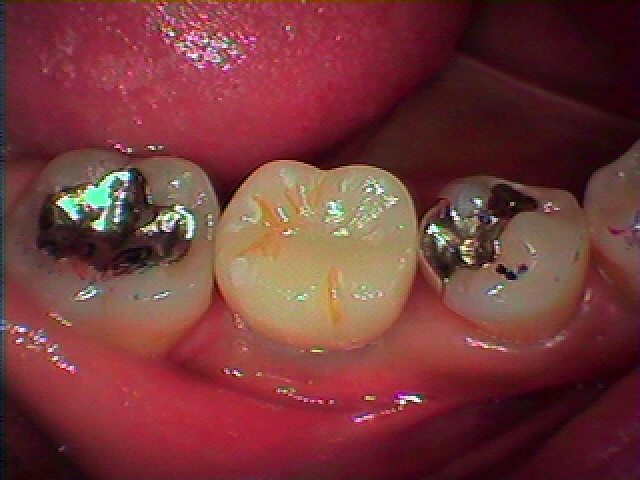

1年後になります

変わらずの色調、マージンの位置を保っています